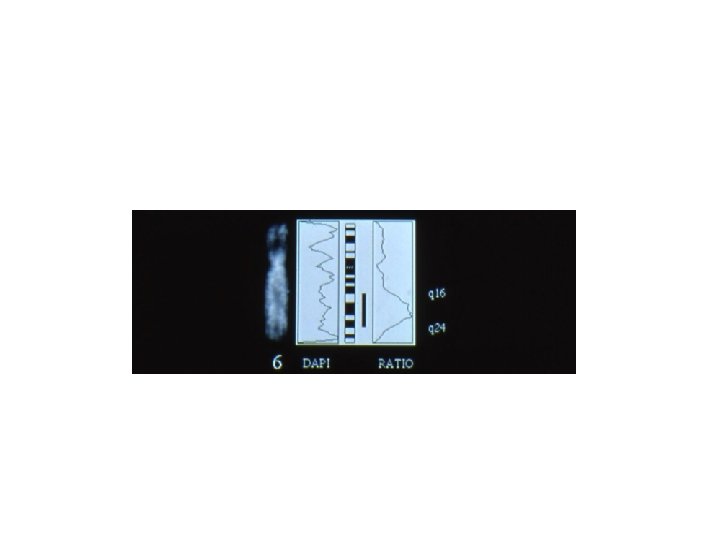

Comparative Genomic Hybridization (CGH) • Comparative genomic hybridization (CGH) is a fluorescent molecular cytogenetic technique that identifies DNA gains and losses, mapping these variations to normal metaphase chromosomes. • It is a powerful tool for screening chromosomal copy number changes in tumor genomes and has the advantage of analyzing entire genomes within a single experiment. • It is particularly applicable to the study of tumors which do not yield sufficient metaphases for cytogenetic analysis and can be applied to fresh or frozen tissues, cell lines, and archival formalin-fixed paraffin-embedded samples.

CGH is based on quantitative two-color fluorescence in situ hybridization. Equal amounts of differentially labeled tumor genomic DNA and normal reference DNA are mixed together and hybridized under conditions of Cot-1 DNA suppression to normal metaphase spreads. The labeled probes are detected with two different fluorochromes, e. g. , FITC o CY 3 for tumor DNA and TRITC o CY 5 for the normal DNA. The difference in fluorescence Intensities along the chromosomes in the reference metaphase spread are a reflection of the copy number changes of corresponding sequences in the tumor DNA.

CGH has the advantage of requiring only genomic tumor DNA, making it highly useful for cancer cytogenetics, circumventing the need for high quality tumor metaphase spreads. The ability to study archival material allows retrospective analysis which can correlate chromosomal aberrations with the clinical course. Since its introduction in 1992, CGH has been applied to a broad variety of tumor types which have previously defied comprehensive cytogenetic analysis by traditional methods. CGH has, for example: • Revealed consistent genetic imbalances and multiple amplification sites in carcinomas of the brain, colon, prostate, cervix, and breast. For instance: it identified chromosome 7 gain and chromosome 10 loss as landmark aberrations in glioblastomas, and specific gains of chromosomes 1, 8, 17, and 20 and loss of 13 q and 17 p in breast cancer. • Found chromosomal aberrations in human leukemia, lymphoma, and solid tumors has identified non-random tumor and tumor-stage specific genetic changes. This information can guide positional cloning efforts. • Become an important initial screening test for chromosomal gains and losses in solid tumor progression, and the results derived from these experiments can be applied to the development of more specific diagnostics.